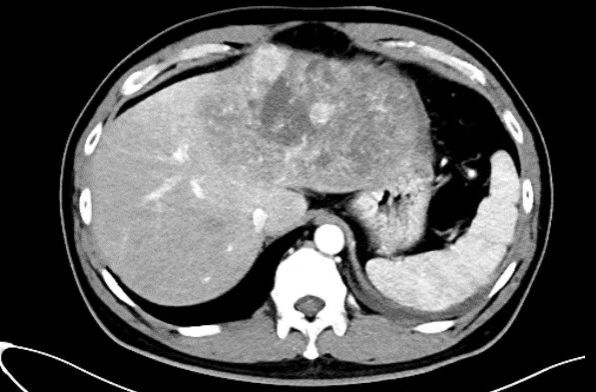

一名四十岁男性患者突发腹痛 1 天由外院转来。患者有慢性乙肝病史,已经多年未做检查,急诊 CT 显示:一个直径约 16 cm×10 cm 的巨大肝癌充满患者左半肝,挤压侵犯第二肝门肝中静脉(图 1,图 2)。更危急的是,肿瘤周围大量积液,怀疑肝癌已发生破裂,患者血压 90/60 mmHg,生命体征岌岌可危。蒋安主任医师接诊后联系输血科董艳迎主任快速输血,迅速纠正休克,使生命体征稳定。